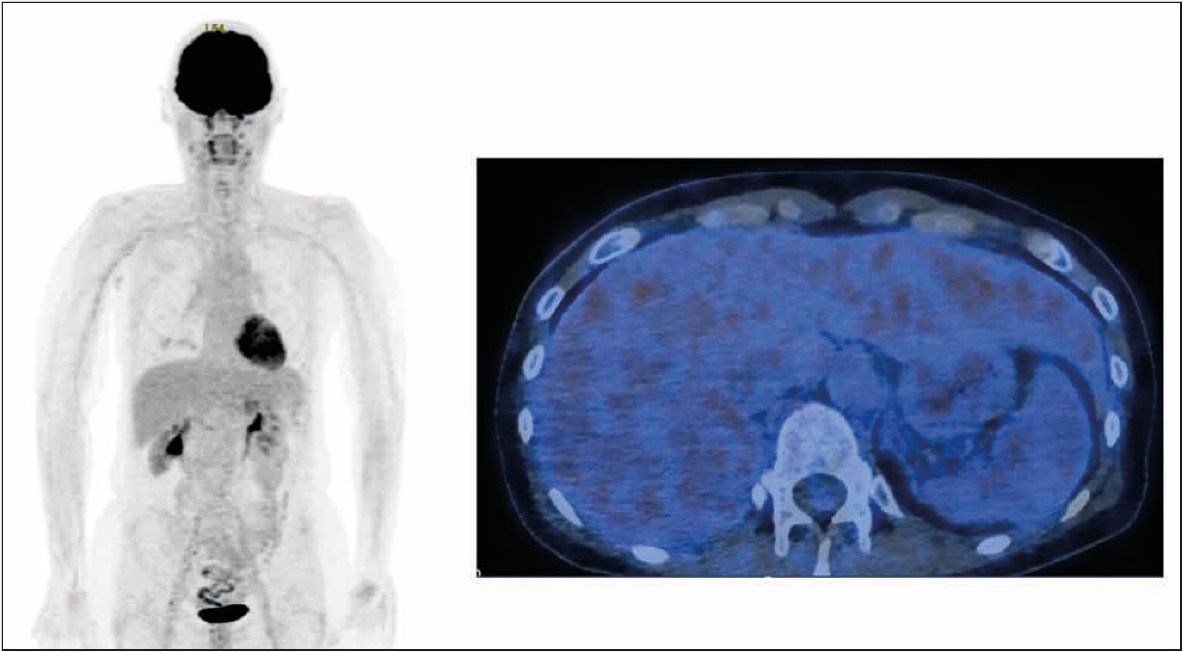

In terms of the treatment benefit, the patient was able to return to her job on a part-time basis in March 2017. Around two months after the end of treatment, from January 2018, the patient reported that her polyneuropathy had slightly improved to grade 1, which was confirmed at the consultation in April 2018. At the same time, a CT scan showed sustained complete remission, which was confirmed by a PET/CT in April 2019 (Figure 2). Apart from the partially pre-existing polyneuropathy, and mild pruritus not requiring treatment, no adverse reactions were observed under treatment with brentuximab vedotin.